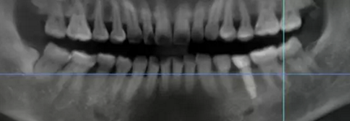

病例概述:48歲女性患者,口內(nèi)健康狀況良好,#35缺失多年,牙槽嵴頂骨寬度較窄。

#35缺失多年,導(dǎo)致#34向#35傾斜。

臨牙間距不足,因此,對種植體的位置要求極高。

術(shù)前術(shù)后CBCT數(shù)據(jù)對比分析,植體就位準確。